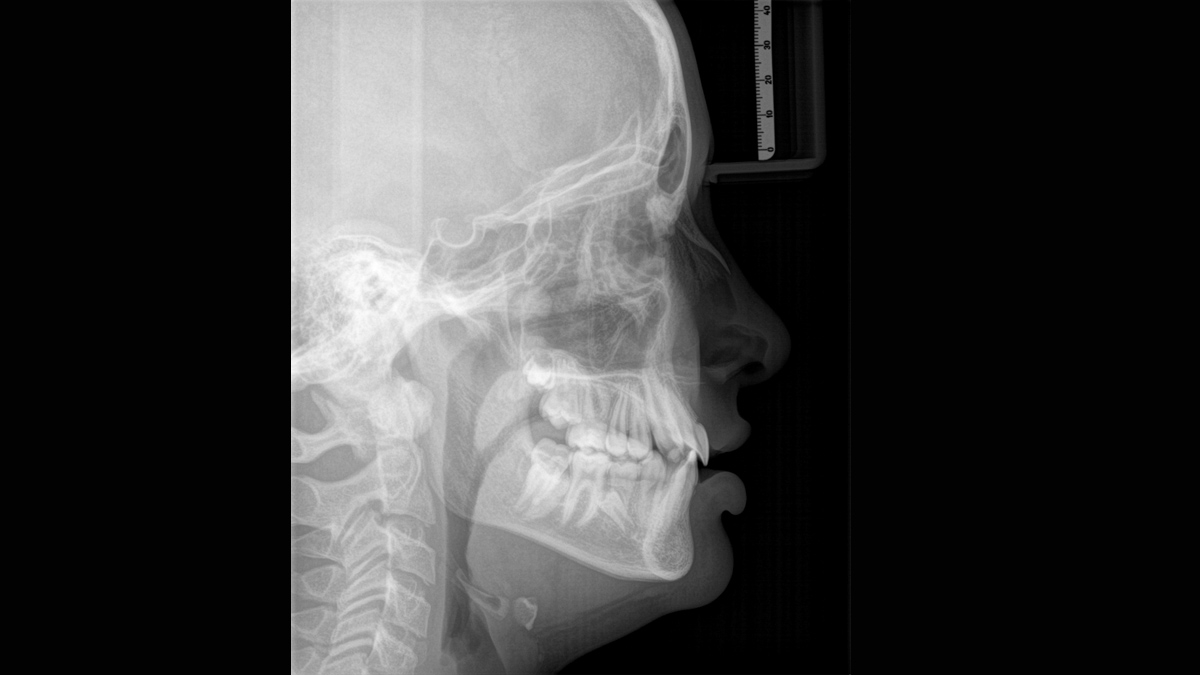

Bras de téléradiographie en option

Clichés PA (postéro-antérieur), AP (antéro-posterieur), et clichés téléradiographiques latéraux avec possibilité supplémentaire de masquer le sommet de la tête et l‘occiput pour réduire encore la dose.

Images bras de téléradiographie :